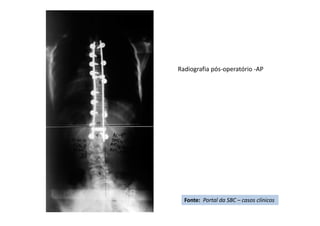

Apresentação de Casos Clínicos

• Escoliose Idiopática do Adolescente

• Resumo do caso: Escoliose idiopática do adolescente tratada

cirurgicamente com artrodese da coluna T4L1 com parafusos

pediculares.

• Paciente (dados): feminino, 13+2 anos, Risser 3, menarca há

9 meses.

• História: Deformidade da coluna percebida pela mãe há 3

meses. Nega tratamento prévio. Nega demais doenças ou uso

de medicações.

• Diagnóstico(s): Escoliose idiopática do adolescente, Lenke

1B-. Tratamento(s): Artrodese da coluna por via posterior T4-

L1 com parafusos pediculares.

• Seguimento ("Follow up"): Seguimento de 2

anos. Literatura:

• Resultado Final: Artrodese seletiva torácica T4-L1, obtida

compensação do tronco e nivelação dos ombros.

Fonte: Portal da SBC – casos clínicos

Radiografia pós-operatório -AP